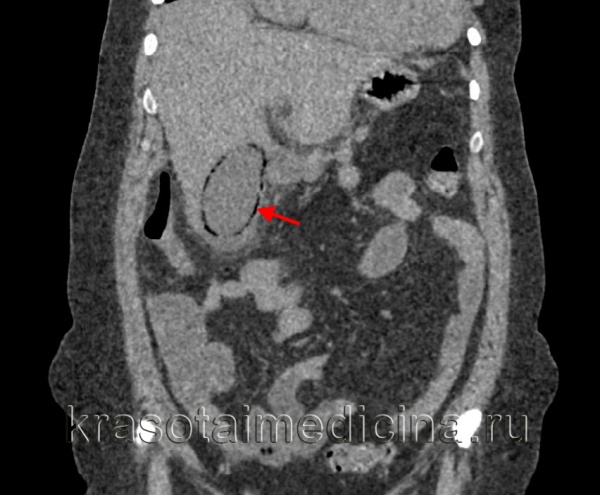

4. КТ при остром калькулезном холецистите:

• КТ с контрастным усилением:

о Неосложненный холецистит:

- Конкременты в шейке желчного пузыря и пузырном протоке

- Утолщение стенки желчного пузыря и субсерозный отек

- Усиление контрастности стенки

- Исчерченность перипузырной жировой клетчатки, перипузырная жидкость

- Регионарная гиперемия печени